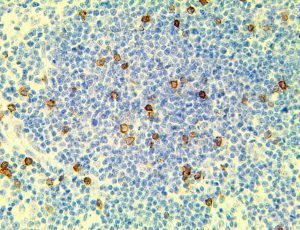

It is the ICU physician who is most likely to witness one of the deadliest manifestations of the abnormal immunological response, the cytokine storm syndrome (CSS). This response is also referred to by some as the cytokine release syndrome (CRS). CSS is characterized by continuous activation and expansion of macrophage and lymphocyte populations, which secrete large amounts of cytokines, causing the cytokine storm. This massive cytokine release is akin to hemophagocytic lymphohistiocytosis (HLH) disease, a syndrome characterized by initial unchecked and persistent activation of cytotoxic T lymphocytes and NK cells.

Clinical and laboratory manifestations of HLH include fever, enlarged liver and/or spleen, neurologic dysfunction, coagulopathy, liver dysfunction, cytopenias (i.e., low levels of erythrocytes, leukocytes, and/or platelets), hypertriglyceridemia, hyperferritinemia, hemophagocytosis, and eventually diminished NK cell activity as the immune system becomes progressively paralyzed. HLH can be familial (primary HLH) or secondary to another disease process (sHLH), such as rheumatic disease, in which it is referred to as macrophage activation syndrome (MAS, characterized by elevated ferritin).